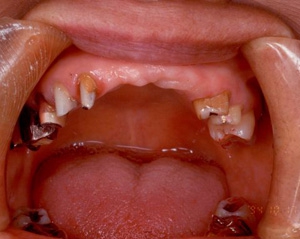

治療前治療前主訴-前歯部の咀嚼不全と審美障害。ブリッジ(固定橋義歯)のために歯を削ったところ 作業模型上のブリッジ作業模型上のブリッジ作業模型上のブリッジ 口腔内装着口腔内装着口腔内装着